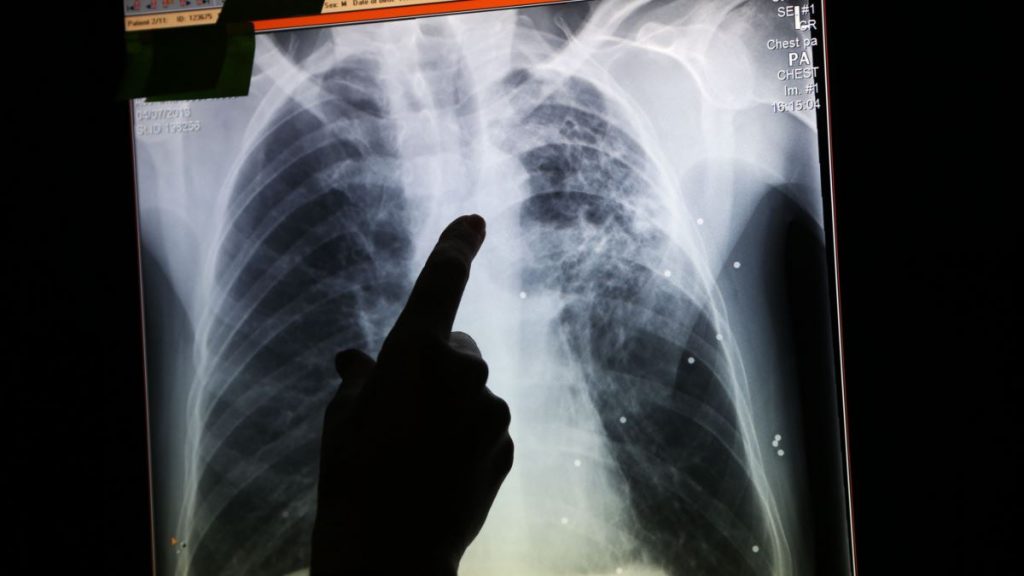

Tuberkulosis paru adalah salah satu jenis tuberkulosis dengan jumlah kejadian terbanyak. Tuberkulosis dapat ditularkan melalui udara dan dropletyang terinfeksi oleh Mycobacterium tuberculosis dari satu individu ke individu yang lain. Menurut data Kementrian Kesehatan tahun 2017, di Surabaya terdapat 2330 kasus tuberkulosis paru, yang terdiri dari 1384 laki-laki dan 946 perempuan. Pengobatan tuberkulosis paru berupa kombinasi obat antibiotik yang diberikan dalam dua fase pengobatan yaitu fase intensif (dua bulan) dan fase lanjutan (lebih dari dua bulan).